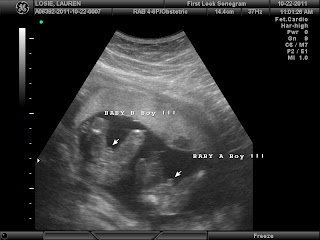

Around 18 weeks we went in for our anatomy scan. They check all of the organs, facial features, weight and bone lengths. This is when they can tell if there are any heart defects or problems with brain development. The tech said they looked very good! One was 10 oz and one was 11oz. So basically I have 1lb 5oz of baby and who knows how many lbs of fluid. It's getting pretty heavy!!!

I go back in a month where they will schedule another anatomy ultrasound to make sure they are still both growing at the right pace. After that I believe I start going more often to check growth and positioning.